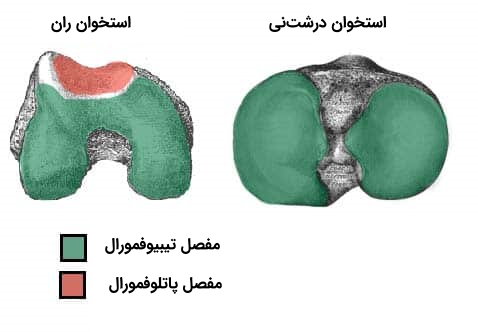

سطوح مفصلی

مفصل زانو دارای سه بخش است که در آنها سطوح مفصلی استخوان ران، استخوان درشتنی و پشت استخوان کشکک زانو به یکدیگر میرسند. در ادامه با این سه بخش آشنا میشویم.

- مفصل بین استخوان ران و درشتنی در سطح داخلی زانو

- مفصل بین استخوان ران و درشتنی در سطح بیرونی زانو

- مفصل بین کشکک و شیار موجود روی استخوان ران

همانطور که میبینیم دو بخش اول مربوط به ارتباط استخوانهای ران و درشت نی هستند، بنابراین بررسی آناتومی زانو به ما نشان میدهد که زانو از دو مفصل ساخته شده است که آنها را با عناوین زیر میشناسیم.

- مفصل تیبیوفمورال: مفصل بین استخوان ران و درشتنی

- مفصل پاتلوفمورال: مفصل بین کشکک و استخوان ران

بررسی سطوح مفصلی برای به دست آوردن درکی درست از آناتومی زانو ضروری است، بنابراین در ادامه با جزئیات ساختاری دو سطح مفصل نام برده شده بیشتر آشنا میشویم.

مفصل تیبیوفمورال

مفصل پاتلوفمورال